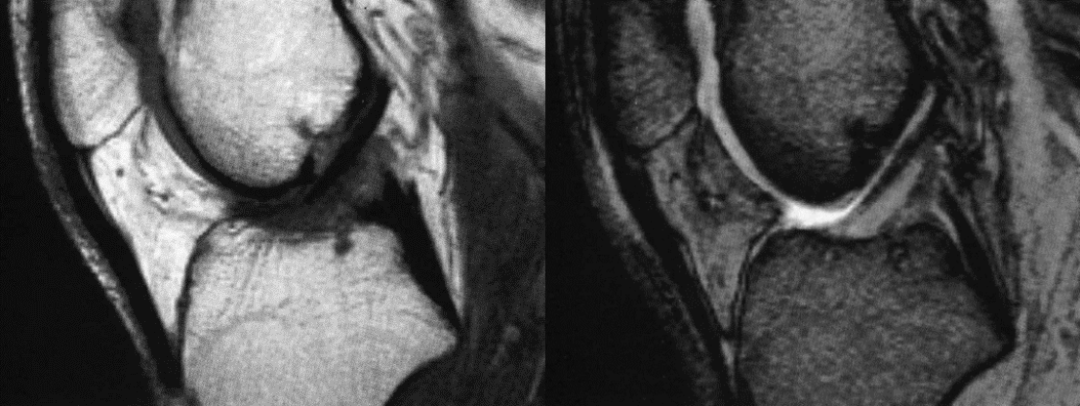

男,30 岁,正常前交叉韧带,T1 及 T2 加权序列矢状面

女,20 岁,正常前交叉韧带,扇形,韧带前为低信号,后为中等信号纤维束